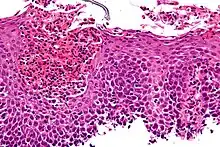

| Micrograph showing eosinophilic esophagitis. H&E stain. | |

At a tissue level, EoE is characterized by a dense infiltrate with white blood cells of the eosinophil type into the epithelial lining of the esophagus. This is thought to be an allergic reaction against ingested food, based on the important role eosinophils play in allergic reactions. The eosinophils are recruited into the tissue in response to local production of eotaxin-3 by IL-13 stimulated esophageal epithelial cells.[3]

Endoscopically, ridges, furrows, or rings may be seen in the esophageal wall. Sometimes, multiple rings may occur in the esophagus, leading to the term "corrugated esophagus" or "feline esophagus" due to similarity of the rings to the cat esophagus. Presence of white exudates in esophagus is also suggestive of the diagnosis.[13] On biopsy taken at the time of endoscopy, numerous eosinophils can be seen in the superficial epithelium. A minimum of 15 eosinophils per high-power field are required to make the diagnosis. Eosinophilic inflammation is not limited to the esophagus alone, and does extend through the whole gastrointestinal tract. Profoundly degranulated eosinophils may also be present, as may micro-abscesses and an expansion of the basal layer.[3][10]

Esophageal mucosal biopsy

Endoscopic mucosal biopsy remains the gold standard diagnostic test for EoE, and is required to confirm the diagnosis.[8] Endoscopy with biopsies of the esophagus has a 100% sensitivity and 96% specificity for the diagnosis of eosinophilic esophagitis.[8] Biopsy specimens from both the proximal/mid and distal esophagus should be obtained regardless of the gross appearance of the mucosa. Specimens should also be obtained from areas revealing endoscopic abnormalities.[2] 2-4 biopsies should be obtained from both the proximal and distal esophagus to obtain adequate tissue samples for the detection of EoE.[2] A definitive diagnosis of EoE is based on the presence of at least 15 eosinophils/HPF in the esophageal biopsies of patients with exclusion of other causes of eosinophilia in the esophagus including gastroesophageal reflux disease (GERD), achalasia hypereosinophilic syndrome, Crohn's disease, infections, pill esophagitis, or graft vs host disease.[8] Endoscopy is usually indicated after treatment is started for EoE to confirm histologic remission.[8]